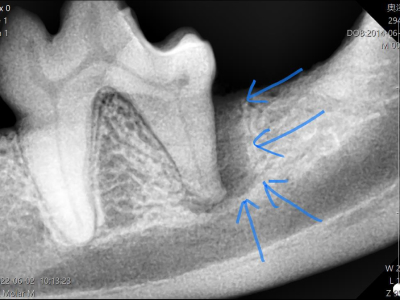

治療前X線

X線で確認するとやはり根っこの周りの骨が歯周病によりなくなっています。